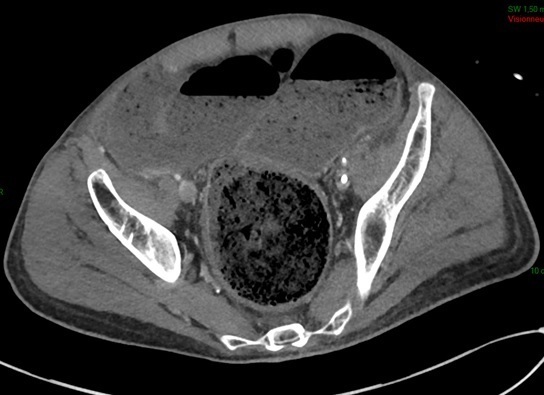

En réexaminant le patient après avoir reçu les résultats de la radio de thorax, vous notez une défense en fosse iliaque gauche. Vous réalisez un scanner abdomino-pelvien.

Question 11 : En visualisant les coupes scannographiques, quelle(s) anomalie(s) identifiez-vous ?

Les coupes montrent une importante distension digestive, principalement colique, avec des niveaux hydro-aériques, dont la cause est un volumineux fécalome.

Le radiologue conclut à un syndrome occlusif.

Question 12 : En visualisant les coupes scannographiques (figures 4), quelle vous semble en être la cause ?

Le siège de l’occlusion est bas, car tout le côlon est dilaté jusqu’au sigmoïde. On voit un volumineux fécalome rectal (figure 4C).